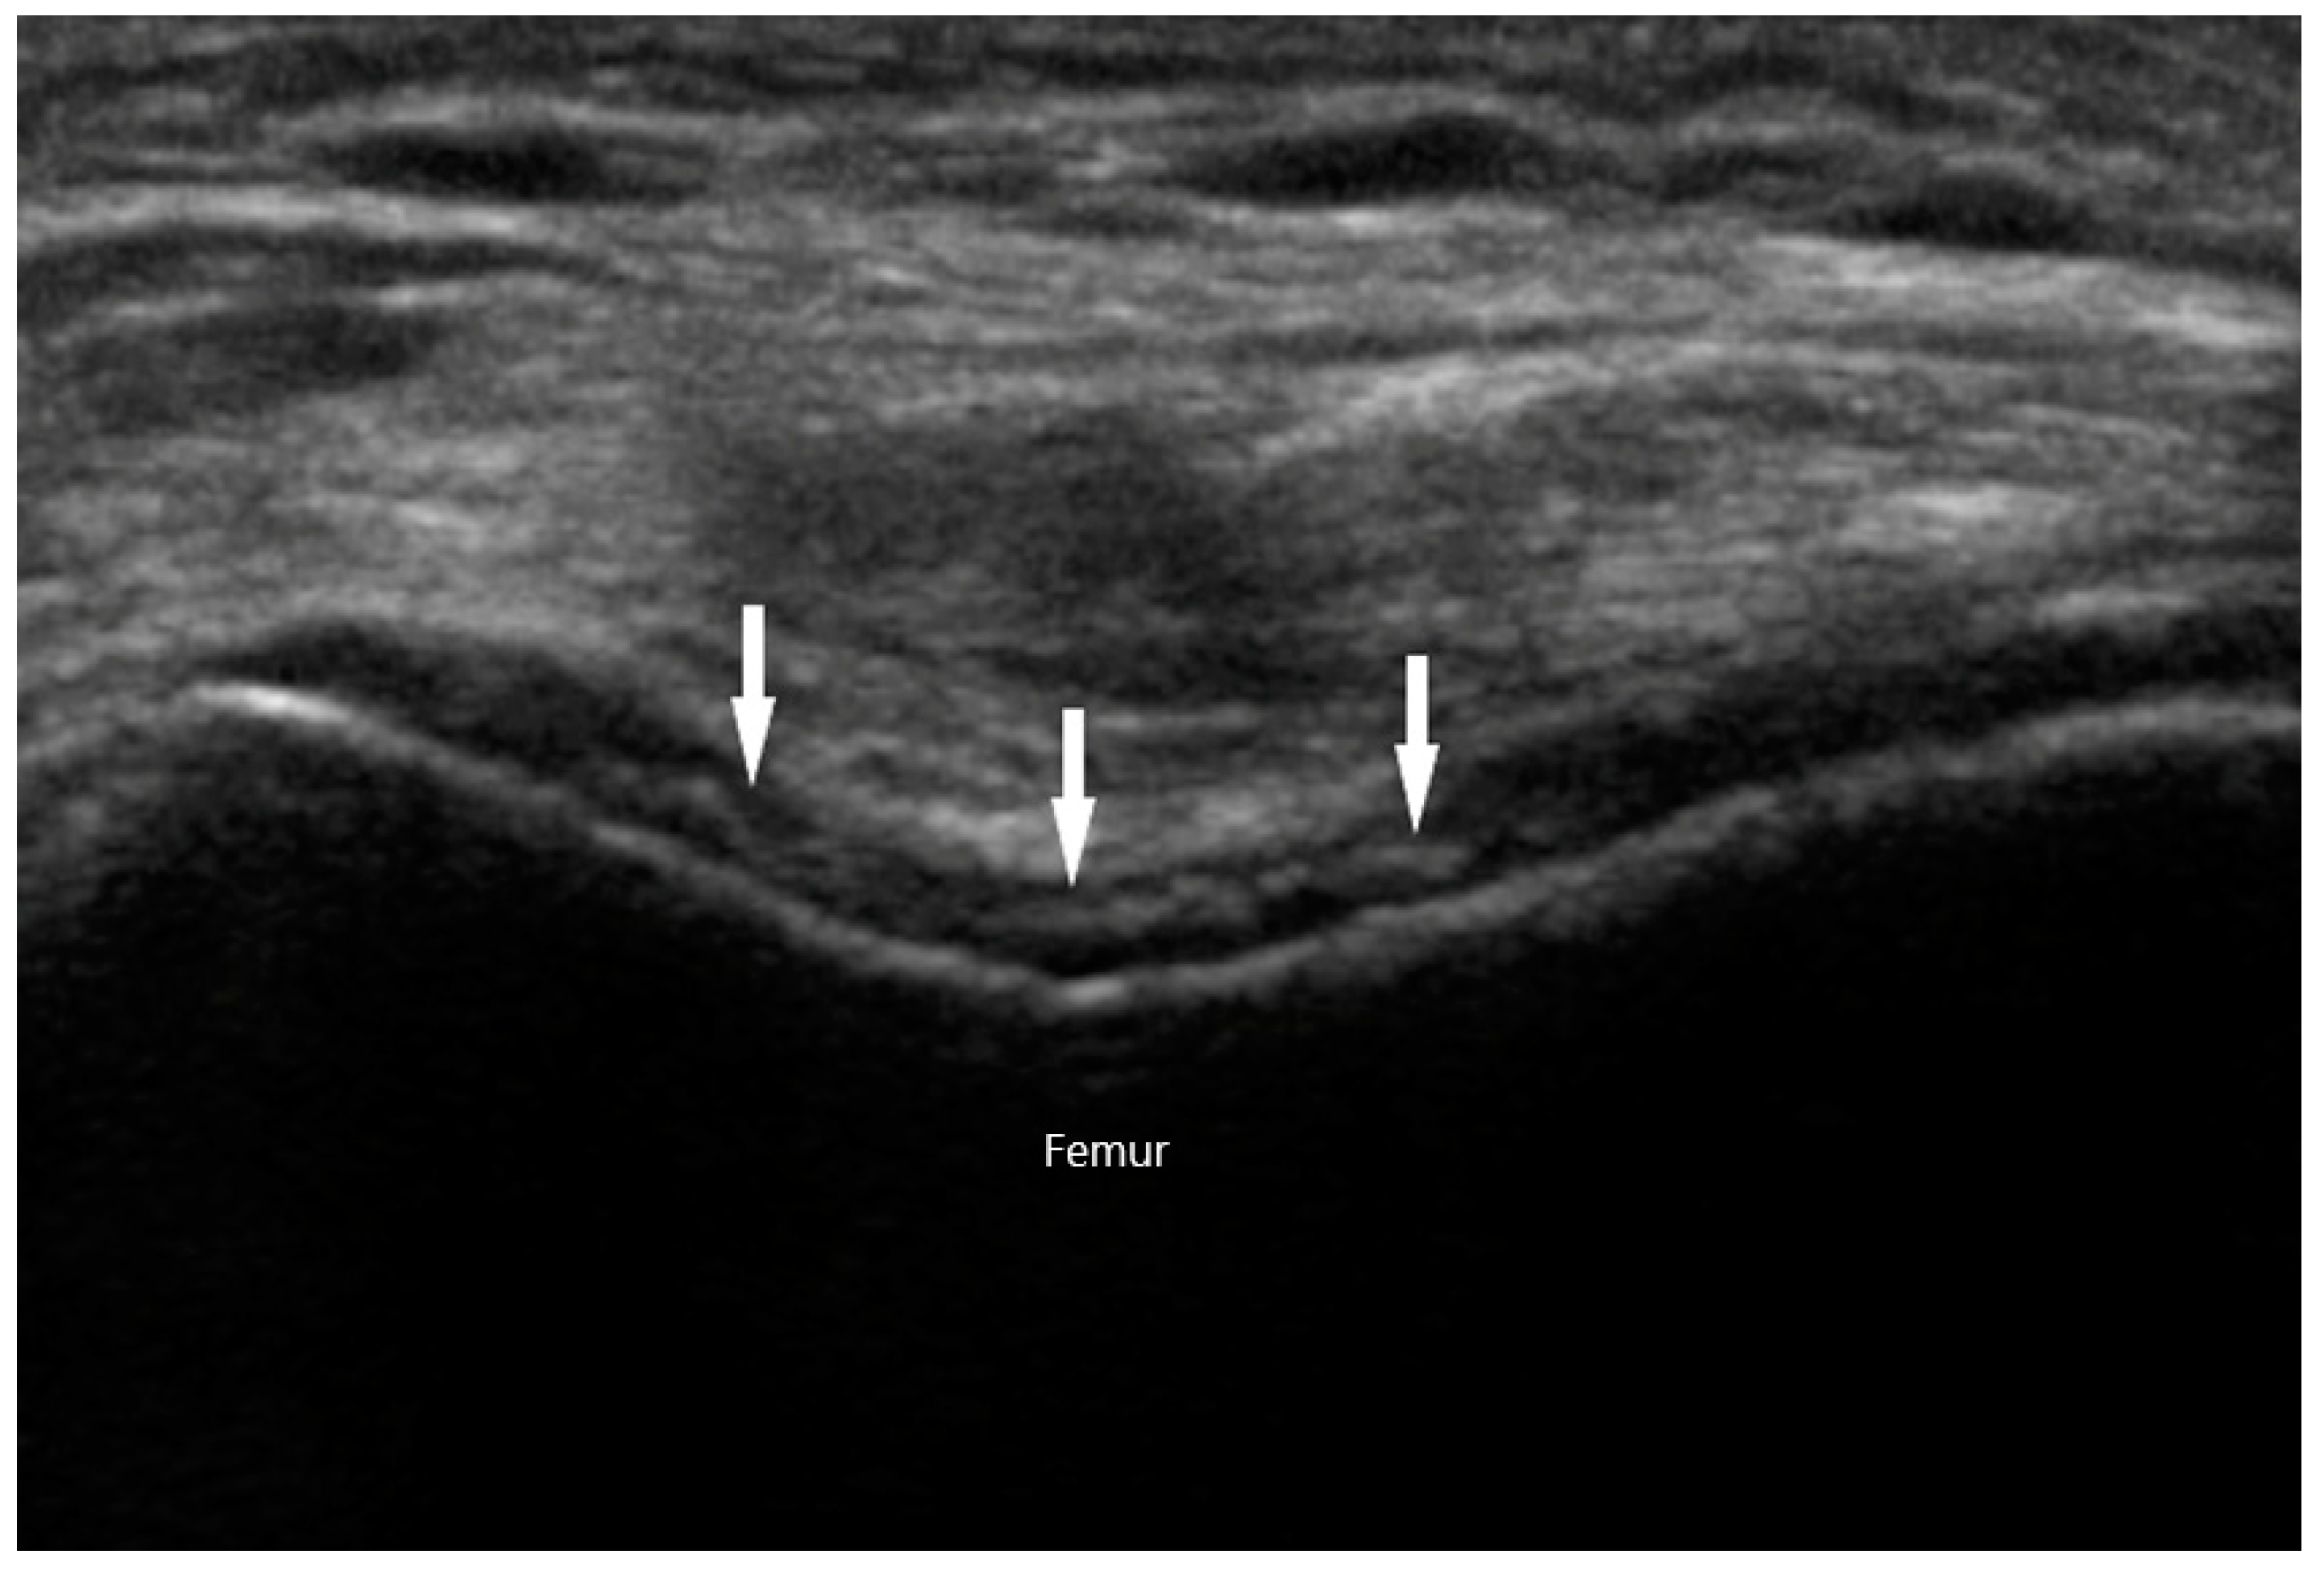

MSU crystals can be seen easily via US as they reflect US waves. They typically appear to be hyperechoic on the superficial margin of the cartilage in either a homogenous or irregular distribution, typically referred to as a “double contour” sign [53] (Figure 9). Any joint can exhibit this finding, but it is most commonly seen in the suprapatellar short axis view of the knee when placed in a flexed position. This ultrasonographic finding is highly suggestive of gout, with a specificity of 97.3% and a positive predictive value of 93.3%. The sensitivity and negative predictive value, on the other hand, is low at 36.8% and 60% respectively [54]. When using the “double contour” sign, one common pitfall is the occasional smooth, hyperechoic appearance of the surface of hyaline cartilage. While it may appear as a “double contour”, only the part of the cartilage that is perpendicular to the US beam will be visible. In contrast, MSU deposition exhibits a more diffuse and irregular pattern. Gouty bone erosions are more effectively detected via US compared to plain radiographs, with respective rates of 67% and 28% for the first metatarsal phalangeal joint [55].

Chondrocalcinosis refers to articular or periarticular deposition of calcium crystals. It can be detected by various imaging modalities, including radiographs, CT, MRI, and US. Chondrocalcinosis on radiographs is most commonly seen in the wrists, knees, or pelvic symphysis. They appear as amorphous radiopaque material within the joint or surrounding fibrous tissues. Sonographic findings suggestive of CPPD arthropathy include isolated hyperechoic amorphous areas, hyperechoic bands within the cartilage, calcifications within the tendon, or hyperechoic nodular deposits within bursas. In contrast to the gouty “double contour” sign on cartilaginous surfaces, the hyperechoic calcifications in CPPD are seen within the hyaline cartilage itself (Figure 10). In a study examining knees in 74 patients with CPPD, Grassi et al. discovered that calcifications in hyaline cartilage were detected by US at a rate of 59.5%, compared to 45.9% by conventional radiography. Specificity for the finding was 100% [59].

Figure 10. Chondrocalcinosis (arrows) within knee cartilage in calcium pyrophosphate deposition disease.